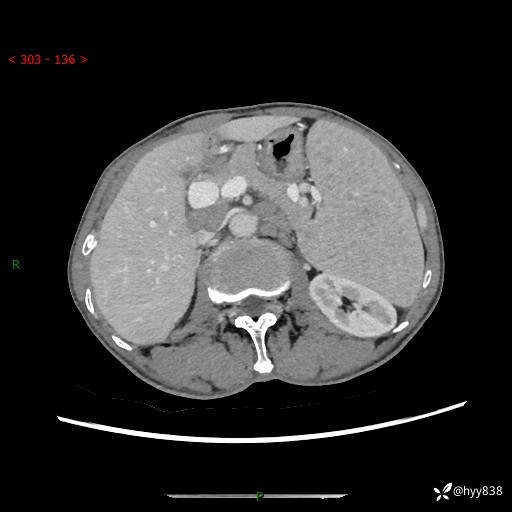

老年男性,脾大并脾脏弥漫粟粒状低密度,淋巴瘤 VS 肉芽肿 VS 血管瘤---结果公布

简要病史: 患者于3月前无明显诱因出现脾大,伴腹部轻微不适,具体不详,无腹痛、腹泻、腹胀,无头晕、头痛、乏力,无恶心、呕吐、呕血,无胸闷、气短、胸痛不适

上腹部CT平扫+增强